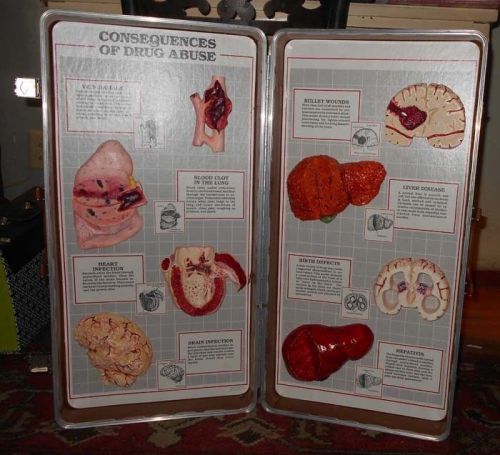

Vintage Consequences of Drug Abuse Medical Display Health Edco Brain on Drugs